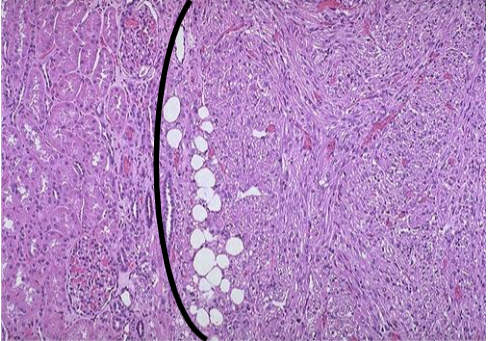

Angiomyolipoma

Benign, but if large may fatally hemorrhage

Neoplasm composed of: Vessels + Smooth muscle + Fat